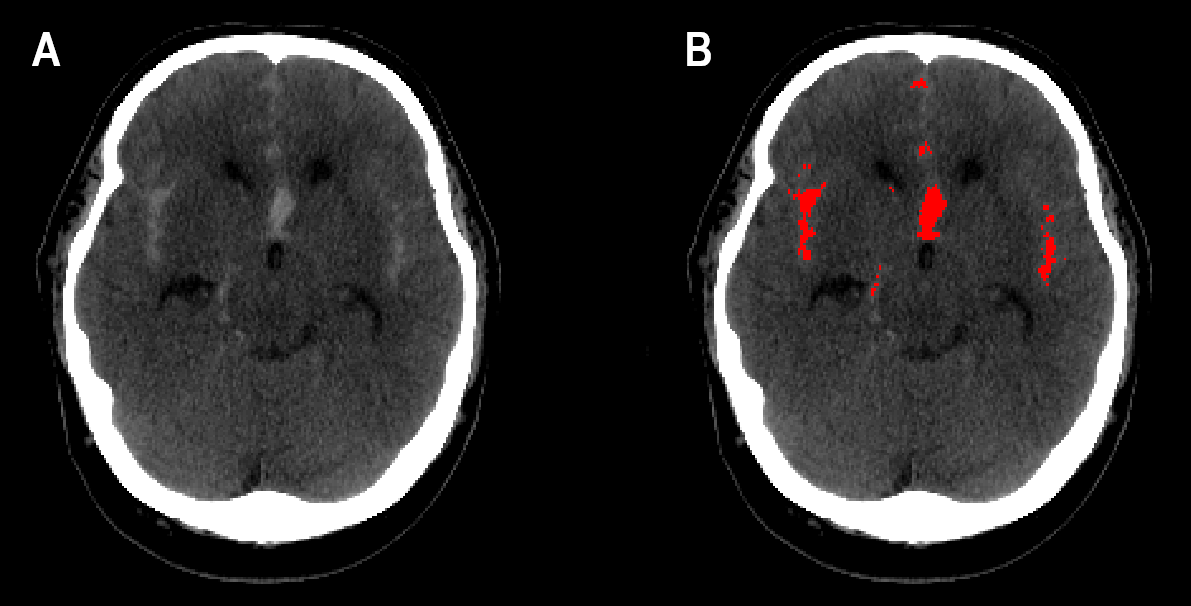

Kuvassa A näkyy pään TT-kuvassa laaja-alainen SAV. Kuvassa B on punaisella merkitty alueet, joissa algoritmi on havainnut verta. (Kuva: HUS)

HUS Helsingin yliopistollisen sairaalan neurokirurgian tutkijat ovat olleet mukana kehittämässä tekoälyyn pohjautuvaa algoritmia, joka tunnistaa tehokkaasti tietokonetomografiakuvista lukinkalvonalaisen aivoverenvuodon (SAV).

Arvostetussa Neurology-lehdessä julkaistussa tutkimuksessa tarkasteltiin tekoälyyn perustuvan algoritmin toimivuutta aivoverenvuotopotilaiden diagnostiikassa. Tekoälyä opetettiin HUSissa hoidossa olleiden potilaiden pään TT-kuvien aineistoon pohjautuen. Tekoälytyökalun toimivuutta tarkasteltiin myös laajemmassa kansainvälisessä aineistossa.

Tekoälytyökalu tunnisti 1 300 TT-kuvauksen aineistosta oikein 136 SAV-tapausta 137:stä. Aineisto koostui yhteensä 49 000 leikekuvasta, joista tekoäly tunnisti SAV-vuodon 1 845 leikekuvassa 2 110 leikkeen joukosta.